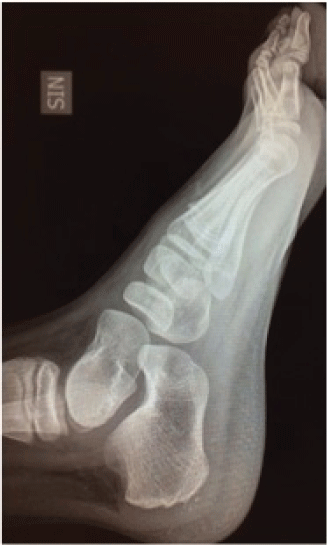

We put the patient through monthly follow-up. He had gradual resolution of the symptoms and was symptom-free at ten months follow-up. Radiographic evaluation performed at this time showed complete reconstitution of the size and trabecular patterns of the medial cuneiforms and tarsal scaphoids (Figure 5, Figure 6A and Figure 6B). The clinical picture had remained unchanged one year later.